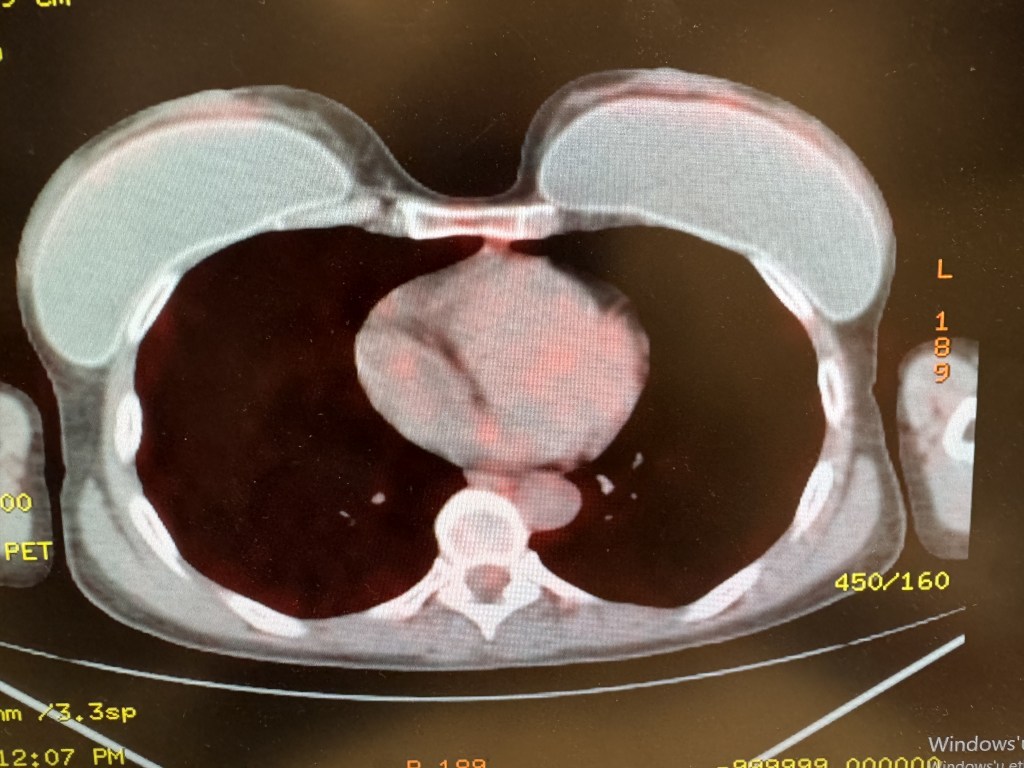

Böbrek üstü bezlerinin metastazlarında veya tanı konulması gereken diğer durumlarda başvurulan sürrenal (adrenal) biyopsi tomografi eşliğinde gerçekleştirilmektedir. Aynı gün taburculuk yapılabilmektedir.